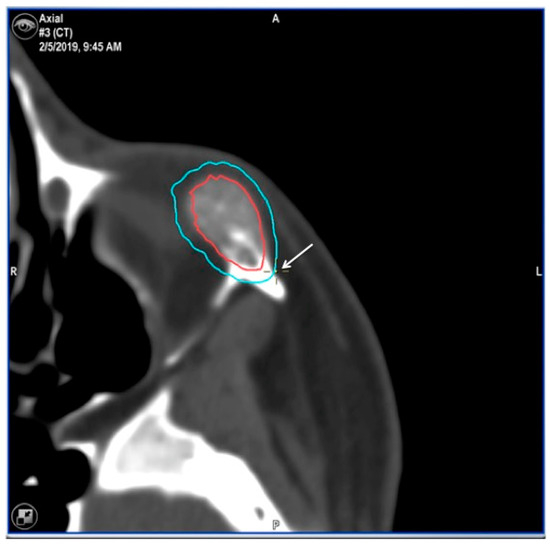

| 1 | 53/F | L/25 mm | Y | 4 mo | Dystopia | N | CT, MRI | Supraorbital rim, orbital roof | Intraosseous venous malformation | - | Resection + reconstruction | Y | Y | 1st, 2nd, 3rd | Coronal | Y | Piezoelectric device | N | PEEK prosthesis | 7 y/N |

| 2 | 54/F | R/33 mm | Y | 9 y | N | Y | CT, MRI | Frontal bone, orbital roof | Intraosseous venous malformation | - | Resection + reconstruction | Y | Y | 1st, 2nd, 3rd | Coronal | Y | Piezoelectric device | N | PEEK prosthesis | 6 y/N |

| 3 | 36/F | L/19 mm | Y | 6 mo | N | N | CT, MRI | Zygoma | Arteriovenous malformation | - | Resection + reconstruction | Y | Y | 1st, 2nd, 3rd | Transconjunctival + blepharoplasty + maxillary vestibular | Y | Piezoelectric device | N | PEEK prosthesis | 5 y/N |

| 4 | 47/M | L/30 mm | N | 2 y | N | N | CT | Zygoma | Intraosseous venous malformation | - | Resection + reconstruction | Y | Y | 1st, 2nd, 3rd | Transconjunctival + lateral canthotomy + maxillary vestibular | Y | Piezoelectric device | N | PEEK prosthesis | 6 y/N |